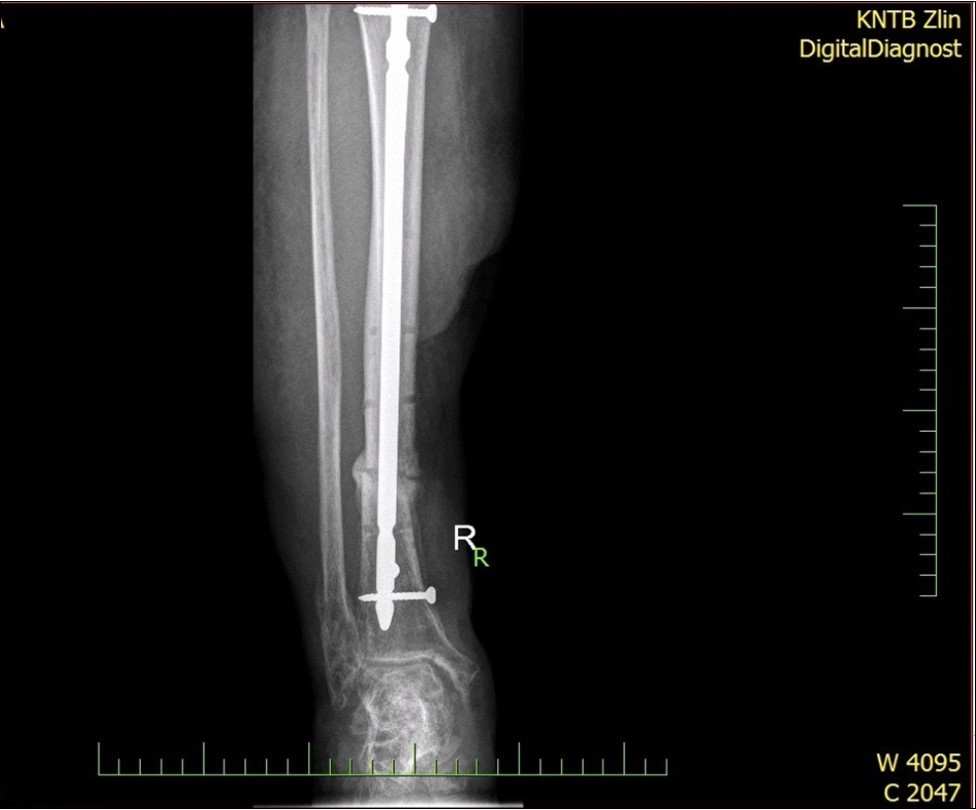

Figure 28.23 April. Surgery conversion of osteosynthesis. Removal external fixator and implantation intramedullary tibial nail. Gradual bone healing - last X-ray september 2019

Figure 29.23 April. Surgery conversion of osteosynthesis. Removal external fixator and implantation intramedullary tibial nail. Gradual bone healing - last X-ray september 2019

Figure 33. X-ray documentation of the whole treatment of tibia fracture. External fixation was used throughout the treatment until bone was healed. From 9.October 2015 to 2.February 2017